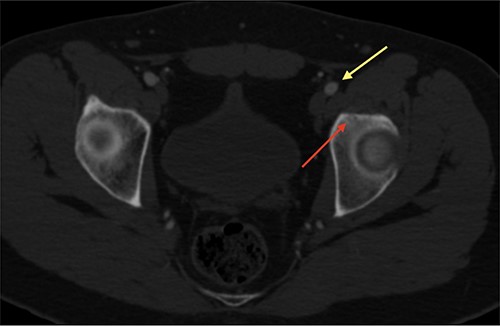

The procedure was made with general anesthesia and in supine position. A 1-cm incision was made for an anterior approach over the hip joint. Careful blunt dissection was done. Percutaneous technique was used with the guidance of a 64 slice Somatom sensation CT scanner (Siemens AG Munich, Germany) with interval cuts of 2 mm to locate the OO. Intravenous contrast was administered to identify the vascular structures at risk (Fig. 3). A 13G × 100 mm bone marrow biopsy needle was used. Image guidance was performed by a senior radiologist (ES). Once the OO was located, accurate insertion of the needle was monitored, and drilling was done manually to help precision in depth (Fig. 4). Multiple bone fragments were obtained and sampled. Immediate image verification showed a space missing the nidus OO. To avoid leaving remnant nidus, curettage was added on the edges and the deep margin of the tumor. Bone samples were sent to histological evaluation and OO diagnosis was confirmed. Wound pain management was administered for 2 weeks and night symptoms disappeared immediately. Complete relief was achieved 3 weeks later. A 12-month follow-up post treatment reported no recurrence of pain and no complications with wound management. ROM and athletic activities are painless. No soft tissue complications were reported.

CT with intravenous contrast showing the femoral vessel (yellow arrow) before the procedure to obtain proper approach (red arrow showing the OO).